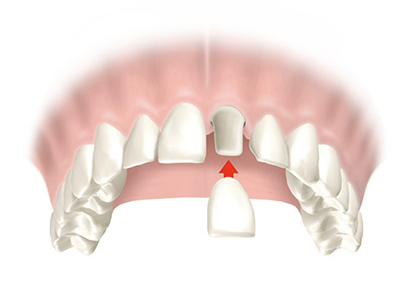

Corona dental

La corona dental es un tipo de prótesis hecha a medida que cubre todo el diente natural deteriorado, con el objetivo de recuperar la función y la estética de la pieza.

Se fabrican con metal-cerámica o completamente libres de metal. El procedimiento se realiza bajo anestesia local y las coronas libres de metal pueden realizarse en sólo un día.

Coronas dentales en un día

- Libres de Metal

- Porcelana de alta estética

- Más resistentes y ligeras